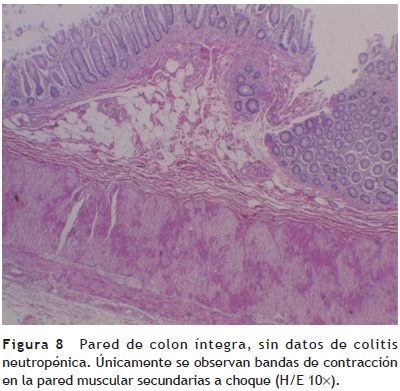

El esófago presentó congestión, sobre todo a nivel del tercio superior, al igual que la mucosa gástrica, la cual conservó sus pliegues. Los cortes histológicos mostraron integridad de la pared, con mucosa conservada, congestión de la submucosa y bandas de contracción a nivel de la pared muscular secundario a choque. El resto del tubo digestivo mostró lo siguiente. En el intestino delgado, se observó ligero aplanamiento de los pliegues, microscópicamente la pared íntegra, únicamente con infiltración adiposa, seguramente porque la paciente presentó sobrepeso secundario a la administración de esteroides. Todos los cortes mostraron mucosa íntegra, depleción del tejido linfoide y congestión de la submucosa. Los diferentes segmentos del colon muestran mucosa íntegra. Llama la atención que no hay datos macroscópicos de colitis neutropénica, no hay presencia de necrosis, y esto se corrobora histológicamente pues la pared y la mucosa se observan completamente íntegras. Únicamente se observaron bandas de contracción en la pared muscular secundarias a choque (fig. 8).